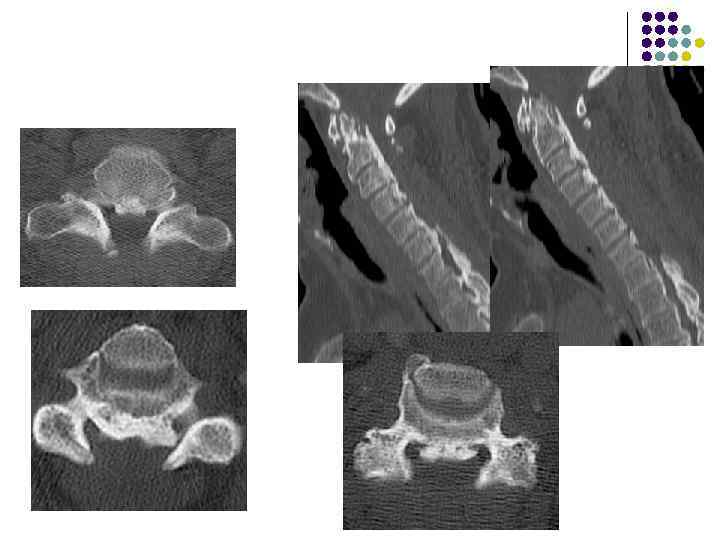

Спондилоартроз Дистрофический процесс в дугоотросчатых сочленениях а) снижение высоты рентгеновской суставной щели б) субхондральный остеосклероз эпифизов в) краевые костные разрастания

Артроз дугоотростчатых суставов из-за перегрузки. В н/поясничных позвонках может развиваться спондилолистез, подвывих в дугоотростчатых суставах, неоартроз (суставной отросток и ножка дуги) Гипер- или гипо- мобильность – увеличение амплитуды нормальных движений (при функциональных пробах)

Артроз дугоотростчатых суставов